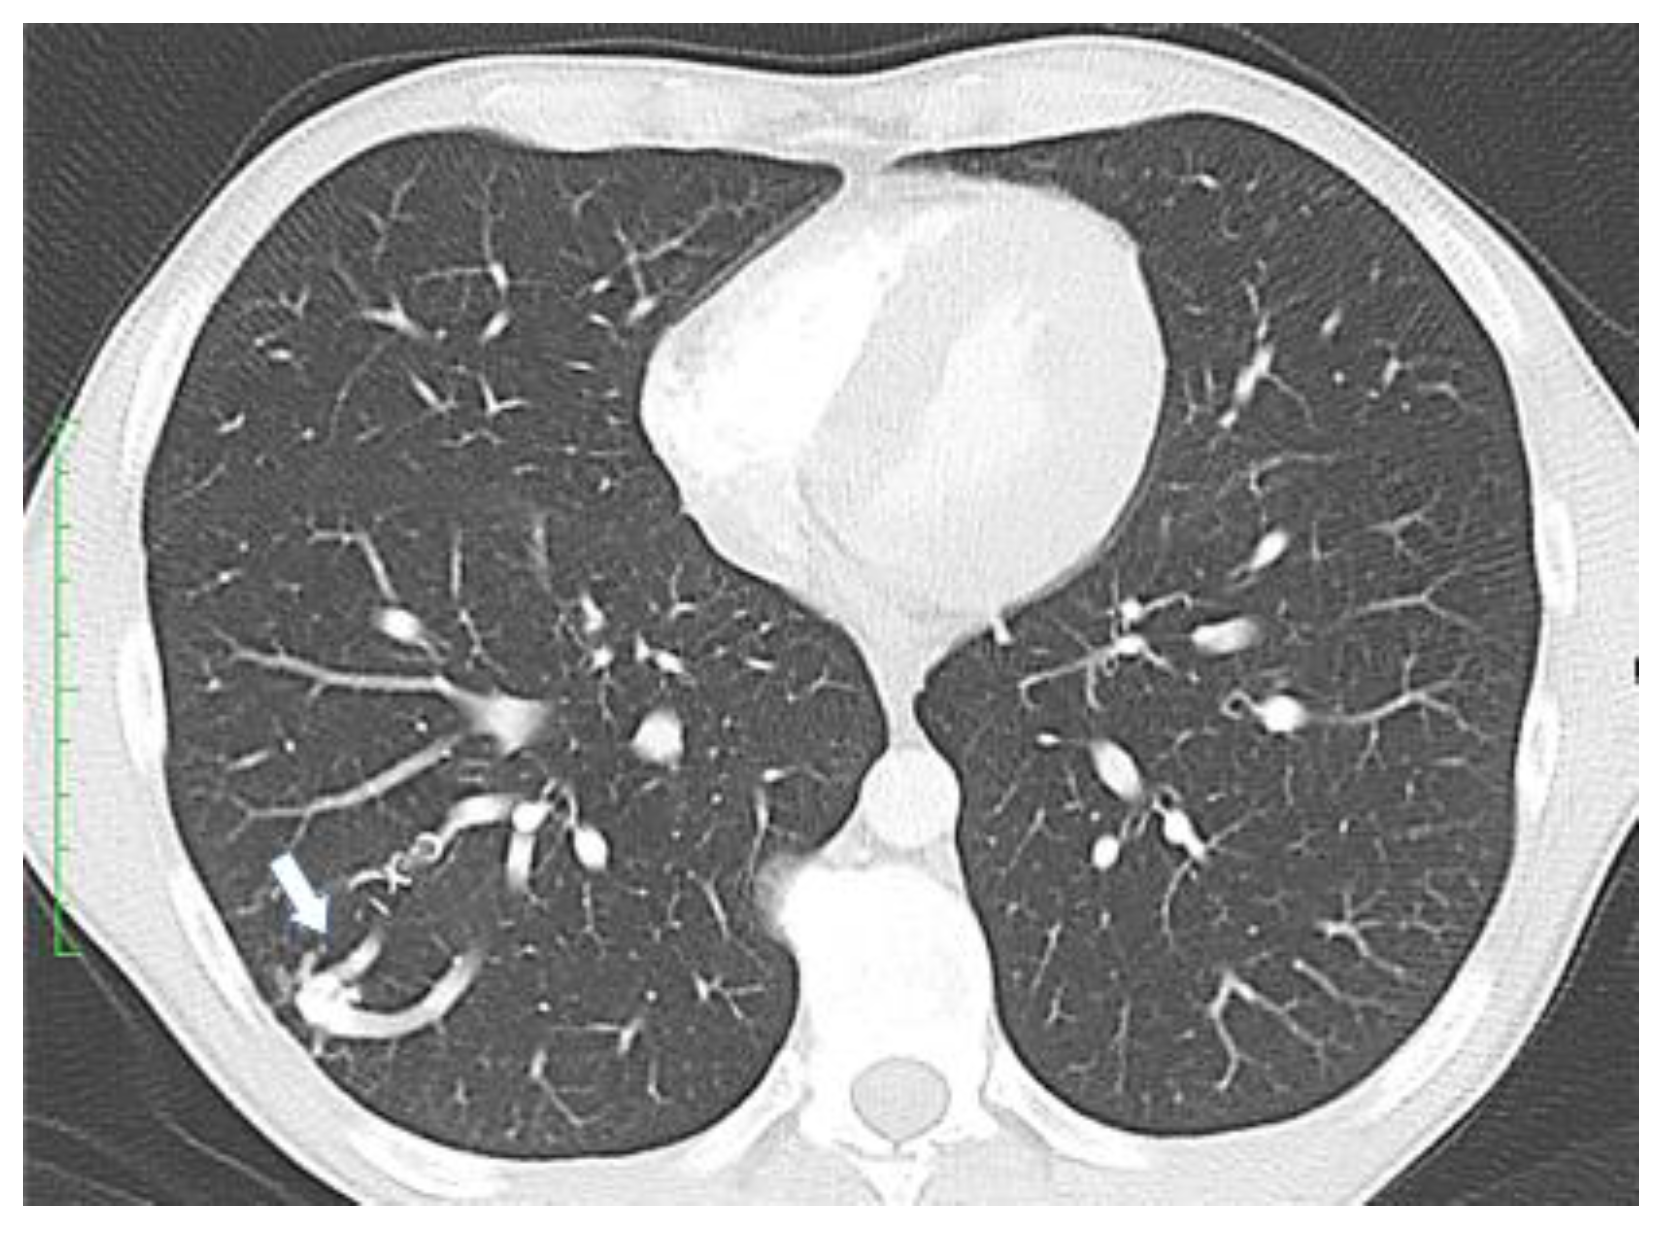

- Visceral lesions: represented by AMVs that may arise in various organs, with characteristic clinical presentations. Gastrointestinal lesions are usually evaluated by upper or lower digestive endoscopies and may become symptomatic through massive hemorrhages or anemia [7]. Pulmonary AVMs can be asymptomatic or may present with bleeding (hemoptysis, hemothorax) or signs of right-to-left shunting such as hypoxemia, cyanosis, poor exercise tolerance, dyspnea, orthodeoxia (decrease in oxygen saturation in an upright posture), nail clubbing, polycythemia, pulmonary embolism, heart failure, and pulmonary hypertension [14]. Neurological symptoms resulting from right-to-left shunting with embolic or infected material through pulmonary AVMs are migraines, transient ischemic attacks, strokes, seizures, and cerebral abscesses. The annual rate for stroke calculated by a meta-analysis is 0.92% and 0.32% for brain abscess [2]. Lesions in the liver may lead to congestive heart failure, portal hypertension, liver failure, and subsequent encephalopathy, and can be evaluated either by Doppler US or CT scan [7]. In the central nervous system, AVMs may be present in the brain or spinal cord and may determine cerebral abscesses, transient ischemic attacks, or even ischemic strokes [7]. These lesions can be examined by angiography or MRI scan.

- Clinicians should screen all patients with a suspected or confirmed HHT diagnosis for pulmonary AVMs.

- Clinicians should use transthoracic contrast echocardiography as the initial screening test for pulmonary AVMs.